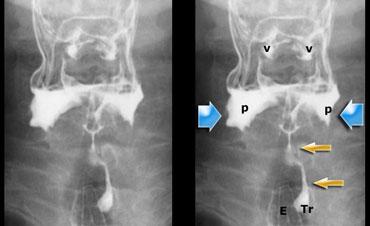

TRÁI: Tư thế nghiêng khi bệnh nhân phát âm “aaa”. Xương móng (H) và nền lưỡi (T) di chuyển ra trước. Xoang hình lê trái và phải được chiếu chồng lên nhau. Đầu mút của màn hầu (SP) được quan sát thấy. PHẢI: Các hố lưỡi-thanh thiệt (V) và xoang hình lê (P).

Hình ảnh đối quang kép của hầu họng

Đối với tư thế nghiêng, yêu cầu bệnh nhân phát âm “aaa”, vì điều này sẽ đưa lưỡi về phía trước và cho phép quan sát tốt hơn vùng hầu miệng và hạ hầu.

Trong tiếng Hà Lan, đây là chữ “eee”, vì được phát âm tương tự như “aaa” trong tiếng Anh.

Đối với tư thế AP, nghiệm pháp Valsalva cải tiến được thực hiện.

Bệnh nhân phải thổi hơi qua môi mím chặt như khi thổi kèn trumpet, đồng thời thư giãn vùng cổ.

Luôn thực hành nghiệm pháp này trước khi thăm khám để bệnh nhân biết cách thực hiện.

Bên trái là hình ảnh đối quang kép của hầu họng.

Sự phồng ra của thành bên hầu họng là bình thường và có thể khá rõ rệt (như trường hợp Dizzy Gillespie).

Những cấu trúc này được gọi là ‘tai hầu bên’ (lateral pharyngeal ears).